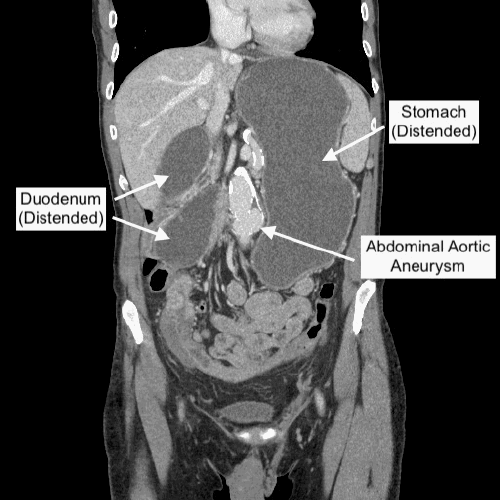

The CT scan revealed a complete proximal small bowel obstruction, characterized by massive fluid distension of the stomach and proximal duodenum, with an abrupt transition point at the level of the transverse duodenum. Notably, the distal duodenum and proximal small bowel loops were abnormally displaced into the right hemiabdomen (Figure 1). An adjacent, calcified abdominal aortic aneurysm (AAA) was also identified. These findings were not typical for common post-colonoscopy complications and prompted urgent surgical consultation.

Figure 1. CT Demonstrating Acute Duodenal Obstruction. Published with Permission

Coronal view from a contrast-enhanced CT scan of the abdomen. The image shows significant dilatation of the stomach and proximal duodenum with an abrupt transition point at the level of the transverse duodenum, consistent with a high-grade small bowel obstruction. Note the abnormal displacement of distal duodenal and proximal jejunal loops into the right abdomen. An adjacent calcified abdominal aortic aneurysm is also partially visualized